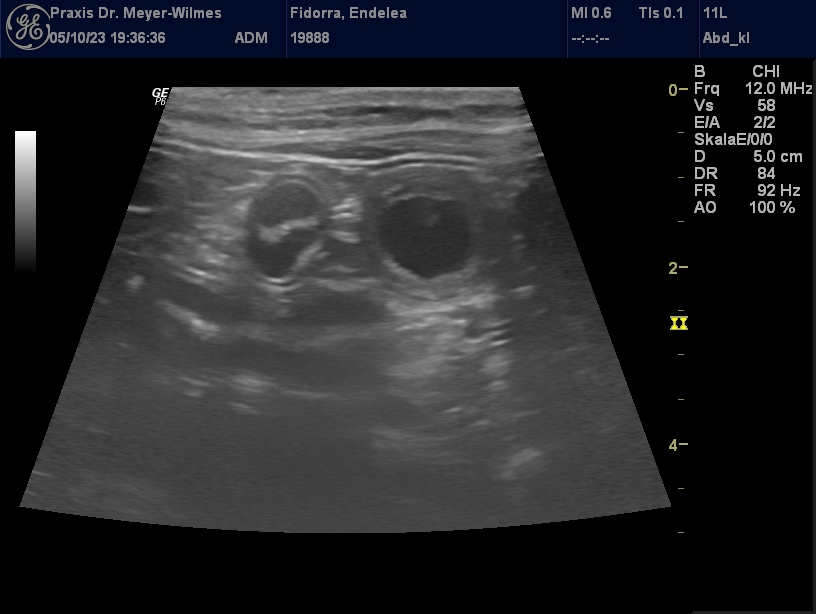

Die kleine Wunder sind bereit zu wachsen und zu gedeihen im Bauch der kleinen Enny:

Endelea und Moyo – sie haben sich “getraut” … Wenn alles klappt, so wie wir es uns wünschen, erwarten wir Mitte November kleine Rhodesian Ridgebacks aus dieser schönen Verpaarung. Endelea und Moyo werden zum zweiten Mal Eltern. Die Kinder aus der ersten Verpaarung sind inzwischen zu tollen wesensstarken und gesunden Ridgebacks herangewachsen, die ihren “Eltern” sehr, sehr viel Freude bereiten …